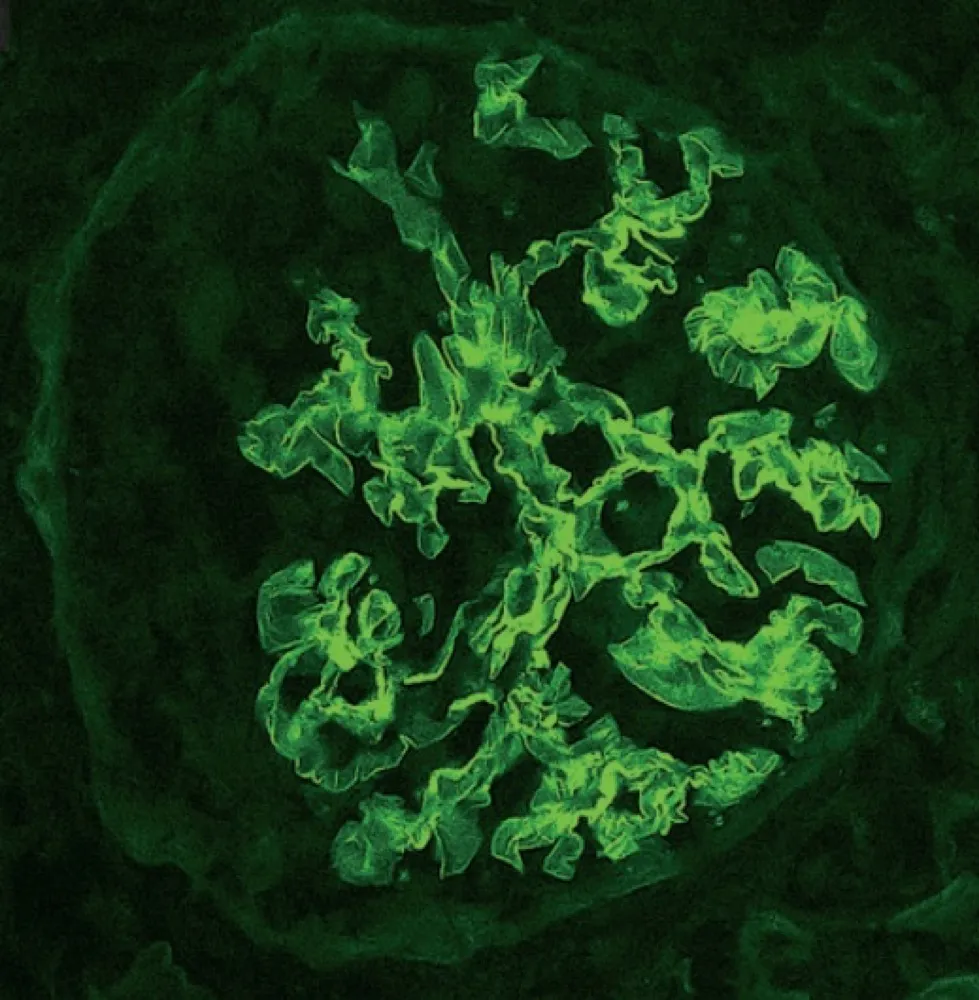

IRA + Icterícia: Um Caso que Exige Investigação Detalhada

IRA + Icterícia: Um Caso que Exige Investigação Detalhada